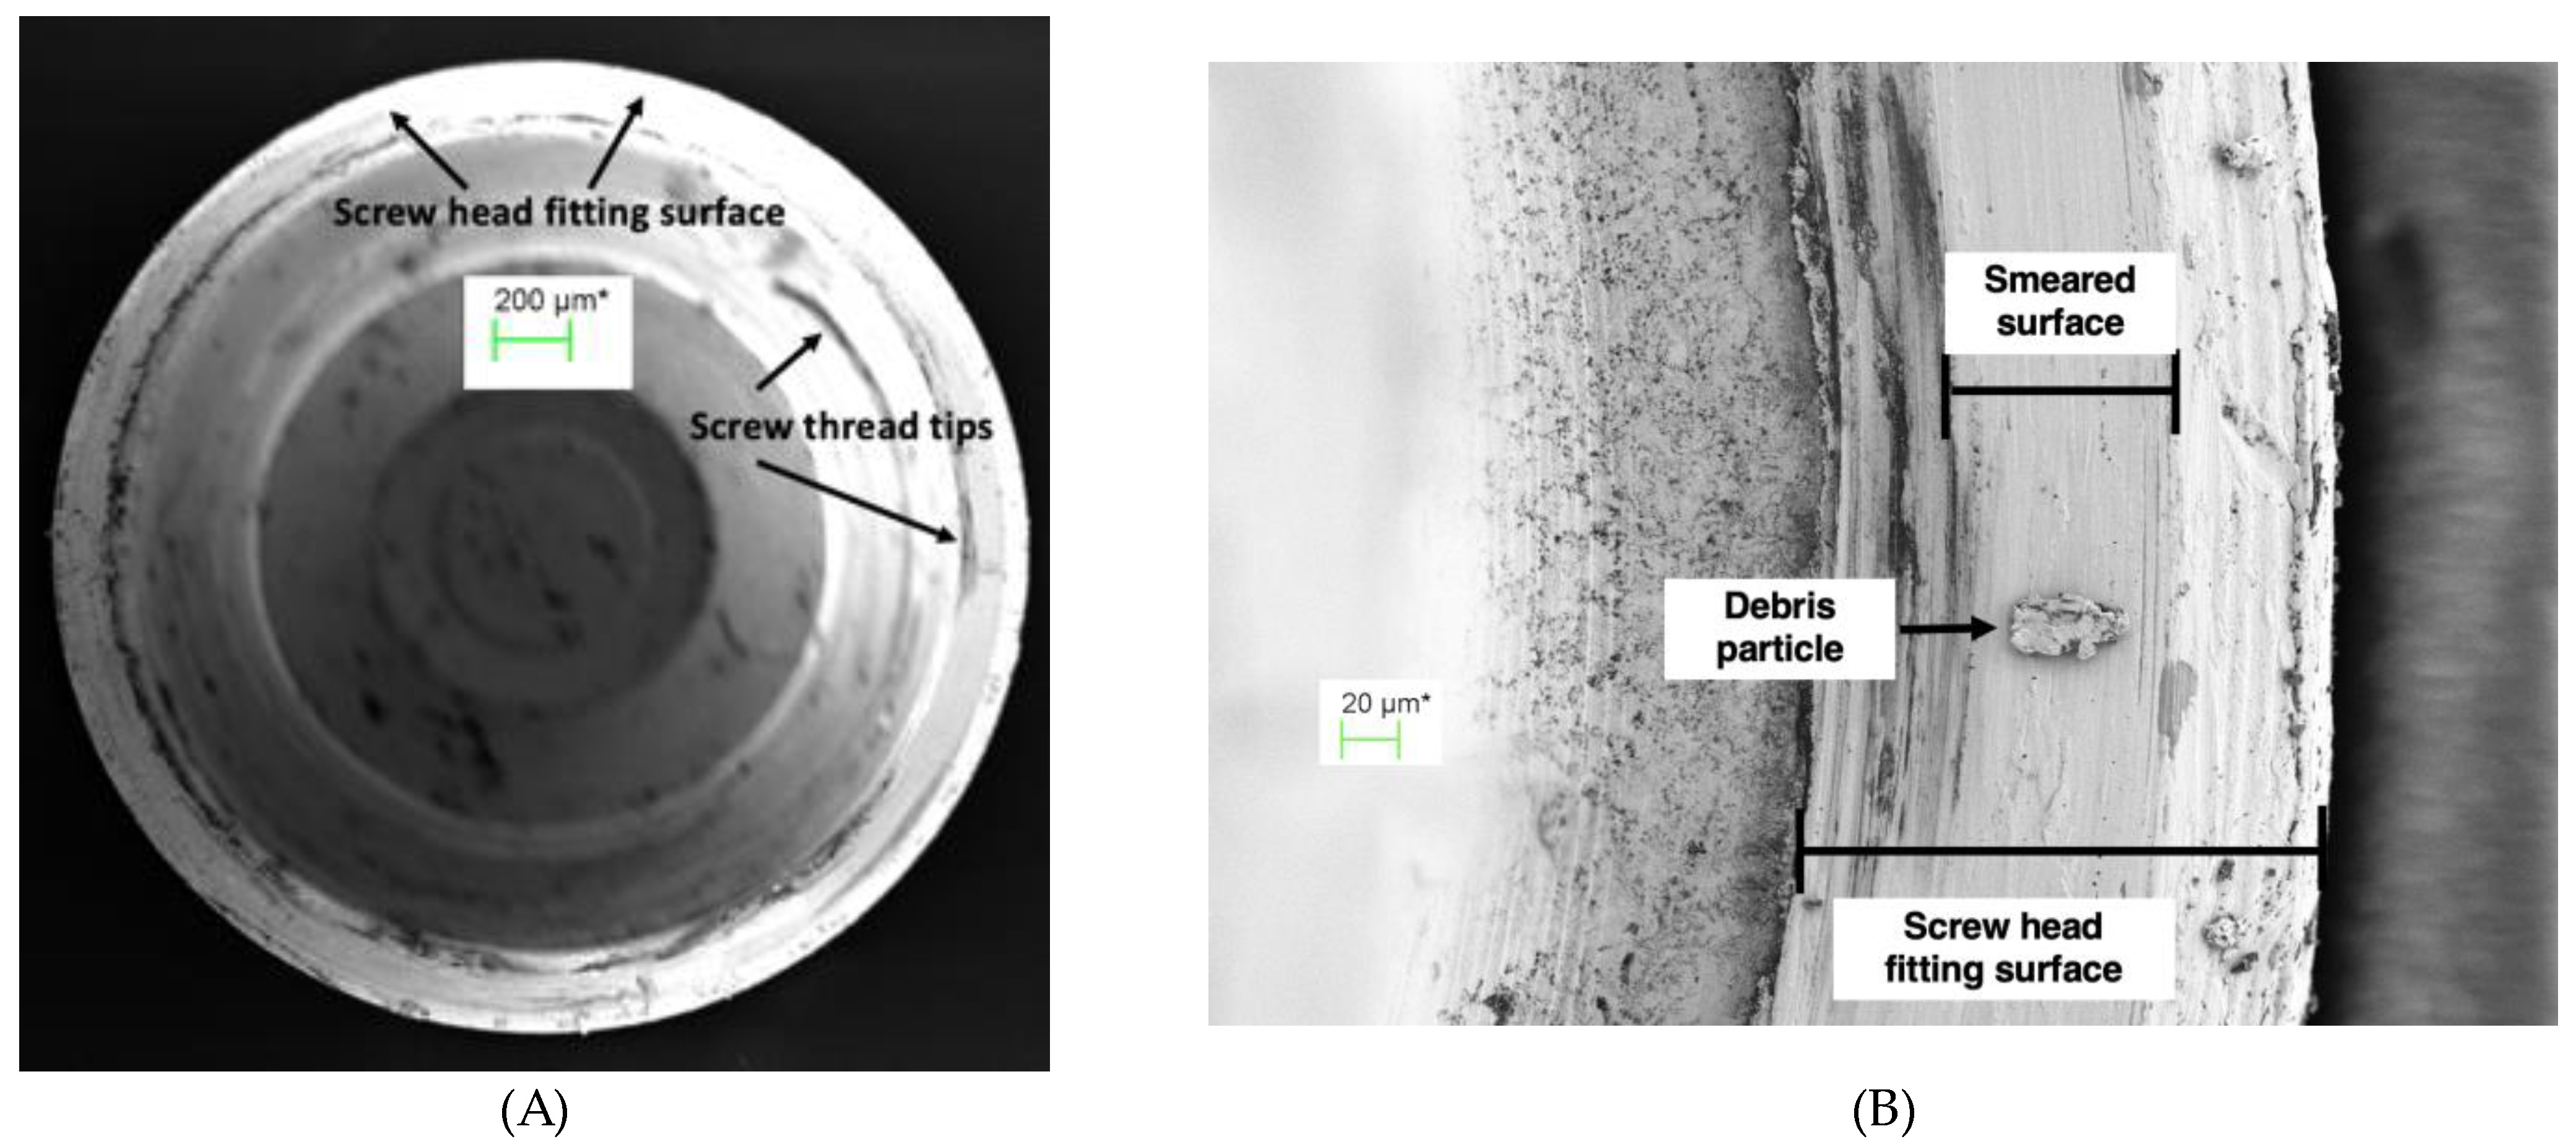

An SEM image at 70 times magnification of the abutment screw seat of TA PUCLA-N5, which showed no E.coli leakage, is shown in Figure 7A. The higher magnification of part of this screw seat (454X) in Figure 7B shows a “smeared” surface indicating an intimate approximation of the surfaces in the region.

Figure 8A shows the opposing surface of the gold plated screw head of TA PUCLA-N5 at 70X magnification. Figure 8B shows a higher magnification (563X) of part of the screw head. Again a smeared section was evident. No bacteria were observed in the abutment cavity indicating there was a continuous smeared region around the circumference of this screw/thread connection, resulting in an initial barrier to the E.coli contamination.

The abutment fitting surface in this specimen also demonstrated a smeared surface region (Figure 9). If this is uninterrupted circumferentially, then it would provide a second barrier against bacterial contamination to the outside of the abutment. As noted previously, in this TA, the screw/thread connection provided an effective seal as there were no bacteria in the abutment space between the screw and implant connection, or in the medium around the micro-gap. Therefore, it was not possible to determine if this was an uninterrupted surface deformation at the implant/abutment connection acting as an additional effective micro-gap barrier to the screw/thread connection.

The other IACs that passed the bacterial leakage test all demonstrated bacteria in the screw chamber indicating a lack of seal at the screw/abutment connection. Therefore, it is assumed that the smeared layer on the abutment fitting surfaces was uninterrupted around the circumference and provided the seal to E.coli transfer into the surrounding medium.

Contrarily, TA PUCLA-P2 failed the leakage test. There was no seal at the screw/thread connection, evidenced by masses of bacteria in the abutment space between the abutment screw seat and abutment fitting surface (Figure 10A). There is evidence of some smearing, but this is obviously not continuous, with bacteria also evident on the outside of the abutment, possibly with remnants of the culture medium. At higher magnification the smeared surface has the appearance of a mosaic pattern with disruptions allowing a pathway for movement of bacteria across the micro-gap (Figure 10B).

The SEM evaluations of the disassembled IACs demonstrated that plastic deformation (smearing) occurred at the screw/thread connection enhancing screw preload as previously documented.[14] However, the extent of this deformation across the connections was variable and does not ensure a continuous seal. Only 1 of the disassembled connections examined had no bacteria in the screw shaft.

The SEM evaluations demonstrated that plastic deformation, or smearing of the abutment abutting surface, also occurred at the IAC with the high noble element content alloy and screw torque protocol used in the study. This was irrespective of whether the abutment abutting surface was gold plated, or whether it was cast or pre-machined. The non-plated abutting surfaces showed a more uniform deformation, whereas the electroplated abutting surfaces showed a more mosaic pattern. This confirms previous speculation.[6] It is postulated that where these smeared regions form a continuous connection around the circumference of the abutment head, an effective seal preventing the egress of bacteria through the micro-gap is achieved. This would explain why some of the connections exhibited an effective barrier to bacterial transfer across the micro-gap at least in the non-loaded scenario. A recently published paper demonstrated a linear relationship between gold plate deposition and plating time with the same alloy used in this study.[23] It is possible that by modifying the plating time, a more consistent deformation and therefore, more consistent bacterial barrier would be achieved in plated surfaces.

Figure 7. (A) Abutment screw seat of TA PUCLA-N5 (70X), (B) Higher magnification (454X) of a section of the screw seat of the abutment of TA PUCLA-N5.

Figure 8. (A) Screw head fitting surface of TA PUCLA-N5 (70X), (B) Higher magnification (563X) of a section of the screw head fitting surface of TA PUCLA-N5 showing a smeared surface which appears continuous.